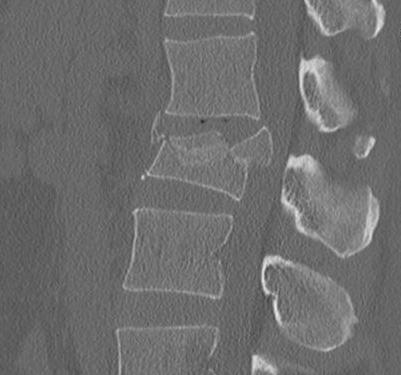

2. Burst Fracture

Characteristics

- axial load

- most common thoracolumbar junction

- retropulsed fragment here causes conus

Definition

- anterior & middle column disrupted

- posterior column injured but no displacement / translation

X-ray

- pedicle widening on AP

- posterior body height decreased on lateral < 50%

CT

Look for canal compromise

- cord signal change

- kyphotic deformity

Retropulsed fragments

- always between pedicles

- typically one or two main fragments (saloon door)

- assess canal compromise